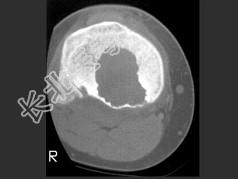

- 单项选择题女,13岁, 右膝部痛,结合图像, 最可能的诊断是 ( )

A、胫骨近端动脉瘤样骨囊肿

B、胫骨近端成软骨细胞瘤

C、胫骨近端骨巨细胞瘤

D、胫骨近端内生软骨瘤

E、以上都不是